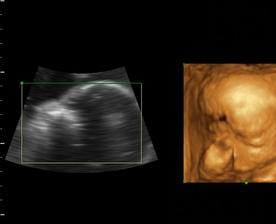

a dnes, 16.10.2008, teda v 38. týždni, padlo definitívne rozhodnutie o mene...skôr moje rozhodnutie ako tatkove...🙂...takže naša prvorodená dcérka sa bude volať Ema Silvia...🙂

a z Emy Silvie je nkoniec Natalka...teraz uz 4 a pol roka, netrpezlivo cakajuca na braceka, ktory restie v brusku...🙂